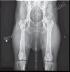

SG Apollo von Nimbus SZ 2154513 HD-OFA: Good

Dagger vom Kriegershaus DN 06768105 HD-OFA: Good